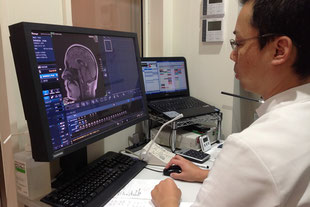

モニターを使った病気の説明

鼻の中の正常構造や、副鼻腔炎という病気については言葉の説明ではイメージがつきにくいものです。正常と病気の時とどのように違うのかなど写真やイラストを使ってモニター上でわかりやすく説明します。

CT、MRI検査(予約制)

内科放射線科 植月医院

医療連携している植月医院に依頼してCT,MRI検査を数日以内で行うことができます。CT検査により副鼻腔炎の状態を細部にまで評価することができ、画像診断専門医の意見を聞きながら病気の診断や状態、治療効果判定などを正確行うことができます。患者さんの状況によっては植月医院からの送迎車を当院もしくはご自宅まで手配することが可能です(午前のみ)。